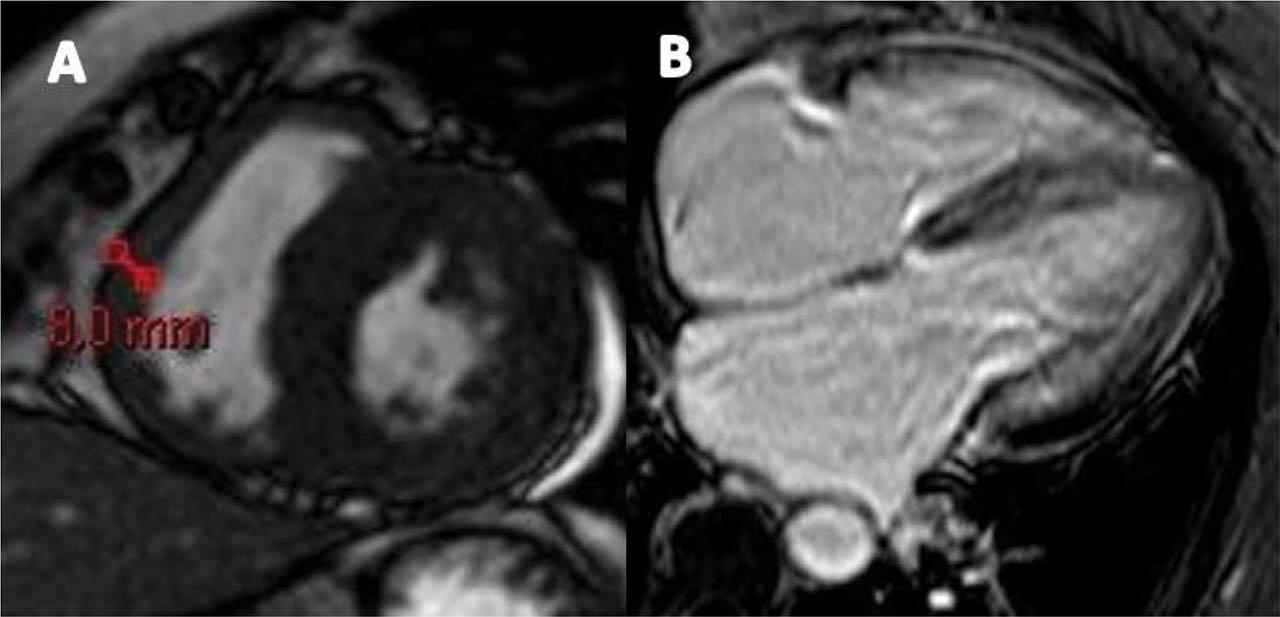

Up to this point, the diagnosis was HF with midrange EF, functional NYHA class IV, due to restrictive cardiomyopathy. Serum cardiac biomarkers were persistently elevated. Moreover, the pseudo-infarct pattern in the anterior and inferior leads on ECG, the discrepancy between low-voltage QRS and increased LV wall thickness on TTE, together with DD grade 3, and apical sparing pattern on STE were suggestive for CA. The patient underwent cardiac magnetic resonance (CMR) which confirmed LV hypertrophy and LVEF of 45%, non-dilated ventricles, enlarged atria (LAVi=66 ml/m2), and 5 mm pericardial effusion adjacent to LV lateral wall. CMR showed diffuse subendocardial late gadolinium enhancement (LGE) at the base and mid-ventricle in the LV and along mitral and tricuspid valve, without LGE involvement of the LV apex and LA (Figure 5). An increase in RV wall thickness was also noted but without LGE (Figure 6). The Query Amyloid Late Enhancement (QALE)12 score was 4 point, highly suggestive of cardiac AL amyloidosis. For histological confirmation, we decided to have a double biopsy, in order to increase sensitivity. Abdominal and rectal pad biopsy were taken and showed homogenous extracellular fibrils positive for Congo red staining and positive for green birefringence, specific for amyloid deposits (Figure 7). Once the diagnosis of CA was made, the next step was to identify the type of amyloid, in order to plan the appropriate treatment. Although serum and urine electrophoresis with immunofixation were negative, a serum free light chains assay showed a marked increase of λ light chains, indicating the presence of a population of plasma cells producing clonal λ free light chains. Because AL amyloidosis was suspected based on CMR findings, a bone marrow biopsy was performed and showed a medullary plasmacytosis (30%), a typical finding for AL amyloidosis.

Figure 5

Cardiac magnetic resonance images showing A and B diffuse subendocardial LGE at the base and mid-ventricle in the left ventricle (yellow arrows). C no LGE of the apex. LGE: late-gadolinium enhancement.

Figure 6

Cardiac magnetic resonance images showing A. an increase in right ventricle wall thickness (8 mm). B no LGE of the right ventricle. LGE: late-gadolinium enhancement.

CMR is also useful for diagnosing CA, particularly when performed with the use of the gadolinium as an imaging agent9. In amyloidosis, LGE can occur in 3 possible patterns: no LGE, sub-endocardial enhancement, and transmural enhancement14. The pattern of LGE may help in differentiating the two subtypes of CA, with transmural LGE being more prevalent in TTR amyloidosis as opposed to sub-endocardial LGE, which appears to be more prevalent in AL amyloidosis14. Moreover, the Query Amyloid Late Enhancement (QALE) score was recently validated as a prognostic score in patients with AL amyloidosis14. QALE score was based on patterns of LGE in the LV at 3 levels (base, mid ventricle, and apex) and in the RV free wall. The maximum LV LGE score at each level is 4 (maximum LV LGE score 12), plus 6 if RV LGE is present and ranged from 0 (no LGE in the left or right ventricle) to 18 (global transmural LV LGE with RV involvement)14. A cut-off of 9 was proved to differentiate prognosis in AL amyloidosis patients with a subendocardial LGE pattern15. Patients with a subendocardial LGE-QALE score < 9 have a better prognosis, similar to the patients with no apparent cardiac involvement and no LGE, whereas a value ≥ 9 implies a worse prognosis, similar to the transmural LGE15. CMR showed subendocardial LGE in our patient, highly suggestive for AL amyloidosis, and the QALE score was 4, with subendocardial LGE observed at the base and mid-cavity of LV, without RV LGE.